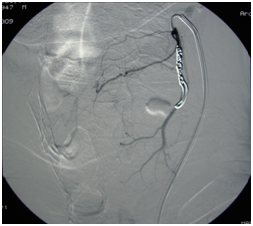

A 62-year-old man was admitted in our Otolaryngology Department of presenting sore throat, disphagia and mild dyspnea after a transesophageal ecocardiography guided cardioversion performed 3 days before. The endoscopic examination of upper aereodigestive tract showed a diffuse soft edema of arytenoids and pharyngolaryngeal tract without airway obstruction. A corticosteroid therapy was started and the symptoms quickly improved but two days later the patient presented suddenly a hemorrhage from the superior aereodigestive tract. The endoscopic examination revealed a swelling of the left lateral wall of the hypopharynx and a hemorrhage from the apex of the swelling witch stopped spontaneous after few minutes. A CT scan of neck revealed an active arterial bleeding with pseudoaneurysmal dilatation of 1,2cm of diameter arising from a fine branch of external carotid artery and a well defined homogeneously enhancing mass, 9.5 x 3.2cm diameter in left neck spaces extending superiorly to parapharyngeal spaces, inferiorly to hypopharynx displacing hyoid bone, thyroid cartilage, posterior to crycoid cartilage displacing cervical esophagus and laterally to subcutaneous tissue displacing sternocleidomastoid muscle (Figure 1). The mass was suggestive for hematoma. The angiography revealed a pseudoaneurysm with active bleeding of the terminal tract of superior thyroid artery (STA) (Figure 2). An endovascular procedure was performed with a superselctive microcateter and a endovascular occlusion by coil embolizzation of STA with exclusion of the pseudoaneurysm demonstrated at the end of the procedure (Figure 3). The symptoms resolved after one day from the endovascular procedure. The patient was discharged after two days without evidence of bleeding and an endoscopic control after 4 weeks revealed a disappearance of swelling.

Figure 2 Angiography illustrating the pseudoaneurysm with active bleeding of the terminal tract of superior thyroid artery (STA).